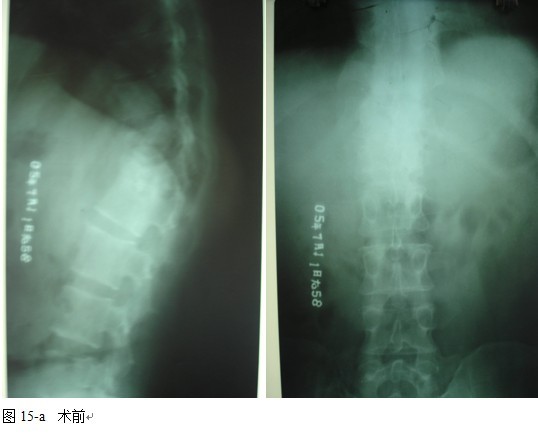

本组46例中男28 例,女18 例。年龄17~67岁,病程6 个月~7年,平均11.3 个月。本组患者均为 L1~S1腰段结核。病灶累及2 个椎体31例(L1-2 6例, L2-3 8例,L3-4 10例,L4-5 5例,L5-S1 2例),3 个或3 个以上椎体15例。合并腰大肌脓肿23列,所有患者均有腰背部疼痛,活动受限,双下肢感觉麻木19例,会阴部感觉减退12例,双下肢肌力减弱12例,腱反射减弱12例,术前后凸角(Cobb 角) <30°者12例, 30°~60°者28 例, >60°者6 例,Cobb角平均32.3°4例患者是二次手术。术前均行X线片、CT或者MRI检查。术后病理检查确诊为脊柱结核。

本组手术用时间3~4h , 平均3.5h 。术中出血300~500ml , 平均约350ml 。术后症状完全缓解,无神经功能障碍加重等并发症,1例营养差的老年患者伤口出现窦道,1例因肝功能差,术后未口服抗痨药,伤口出现窦道,经换药后二期愈合,其余病例伤口均一期愈合。马尾神经受损的患者术后基本恢复正常。术后一周后凸角平均 5.4°后凸畸形平均矫正90%以上, 最终后凸角平均8.3°,后凸角度平均丢失4.2°。随访3个月有87%(40/46)有骨痂形成,6个月91.3%(42/46)明显骨性愈合(见图),其余4例9-12个月内愈合,随访时间3-32个月,平均11个月,46例患者中2例在术后2个月和3个月时背部形成脓肿,换药后治愈。2例出院1月后并发结核性脑膜炎,治疗后好转。1例因椎弓根钉偏外,刺激神经根,5个月后从侧方脱出,疼痛加重,因前后路植骨完全愈合,取出后症状完全缓解。